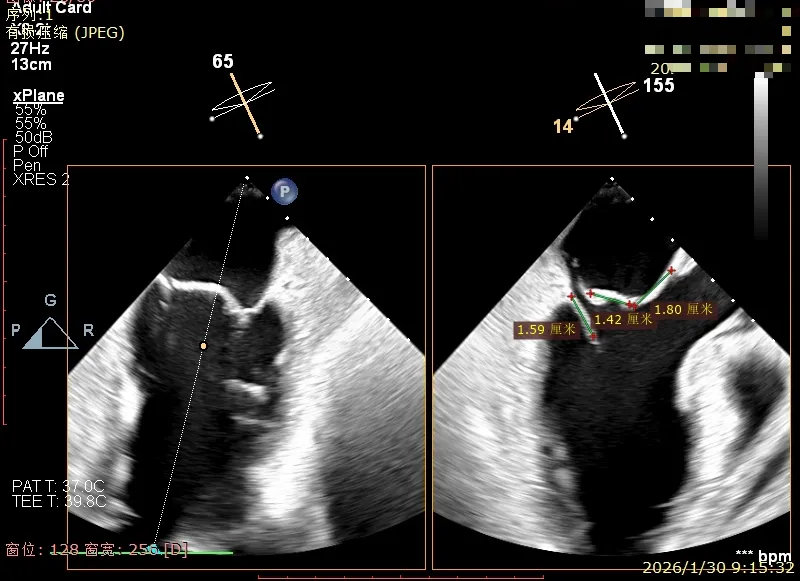

经胸超声报告提示:患者二尖瓣2区及3区前叶关闭时脱入左房,二尖瓣重度反流(MR 4+),患者LA前后径约52mm,LVEDD约68mm,LVESD约42mm,EF值:65%,经胸超声测二尖瓣瓣口面积约6.1cm2,主动脉瓣无冠瓣脱垂并中重度反流,三尖瓣中度反流,估测中度肺动脉高压。

经食道超声精细化测量:肺静脉逆流,房间隔可穿刺高度约4.2cm,Flail宽度约21mm,Flail高度约8mm,Flail Gap约4mm, 3区AML长约23mm、PML长约12mm、2区AML约32.2mm,PML约16mm。

Bicomm切面看2区脱垂

上Color,可见反流主要来自于3区

X-Plane切面切1区未见明显异常

1区上Color,未见反流来源

X-Plane切面切2区可见前叶Flail

2区上Color,可见反流来源

X-Plane切面切3区可见前叶脱垂

3区上Color,可见反流来源

3D Enface 2区及3区前叶脱向左房

3D Enface 可见反流由2区3区从前后冲出

房间隔可穿刺高度约4.2cm

Flail宽度约21mm,Flail高度约8mm

经胸短轴测得瓣口面积约6.1cm2

3区前叶长度约22mm,后叶长度约11.6mm

2区前叶长度约32.2mm,后叶长度约16mm

2区Flail Gap约4mm